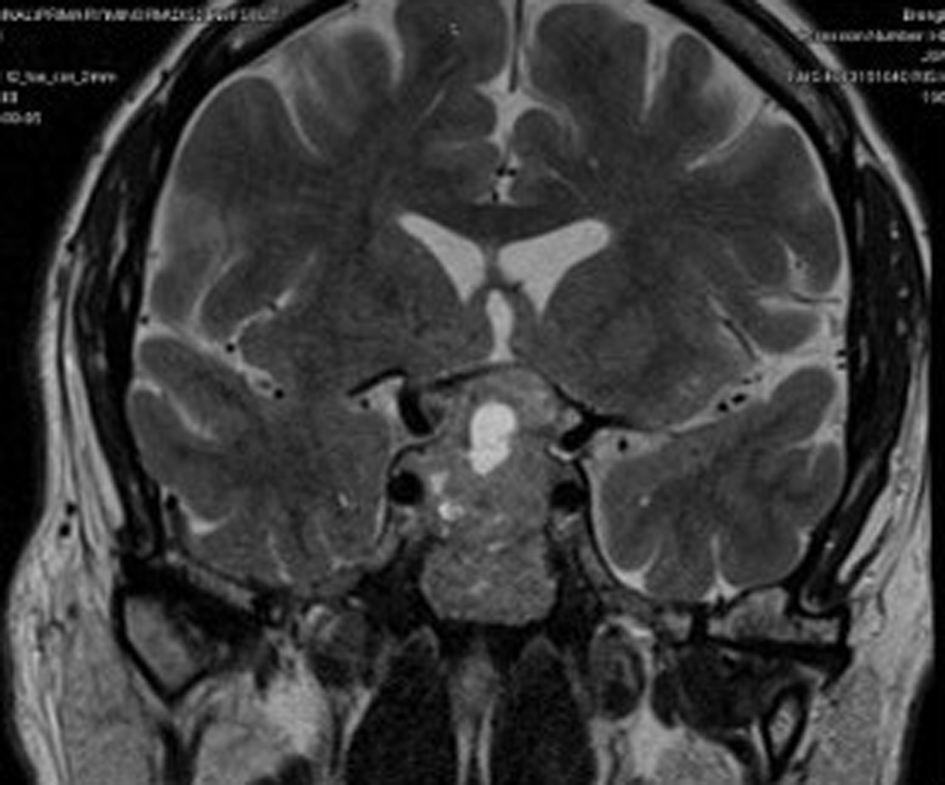

His initial blood investigations (Table 1) showed biochemical evidence of hypopituitarism with T4 of 9.5 pmol/L, FSH of 1.9 IU/L, LH of 2.0 IU/L, testosterone of 4.4 nmol/L, 9 am cortisol of 228 nmol/L and prolactin of 370 mU/L with a temporal field defect in the left eye, confirmed by Humphrey’s perimetry (Figure 1). Pituitary MRI showed evidence of pituitary macroadenoma with suprasellar extension and optic chiasmal compression (Figure 2).

The patient was initially diagnosed with a visual field defect by an ophthalmologist and then was referred to an endocrinologist; detailed history taking showed a picture of gonadotropin deficiency. Patients with NFPA can present with acute deterioration in vision with or without headaches due to haemorrhage into the tumour (known as apoplexy), leading to rapid expansion of the tumour within the limited space of the sella turicia.4 The patient had a left-sided visual field defect, with MRI showing a necrotic area within the tumour with no signs of bleeding or haemorrhage. Although bitemporal hemianopia is the most common type of visual field defect seen in 40% of patients, our patient had left superior and inferior temporal deficits without cranial nerve palsy.5

Some distinctive features to point out in our patient were firstly, it’s a Giant pituitary tumour with central necrotic area, resembling radiological features of pituitary apoplexy, which is a life-threatening condition, presented without headaches or vomiting. Secondly, the tumour was large enough to compress the optic chiasm but had affected the left temporal field sparing the right. Limitations to the study are that, since it is a single case study, the clinical features may vary and validation of our findings to a wider population is needed.